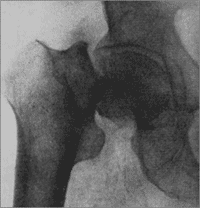

Перелом шейки бедренной костиГлавная » Справочник травма » П » Перелом шейки бедренной кости

Переломы шейки бедренной кости делятся на 2 вида: медиальные и латеральные.

Медиальные переломы шейки бедренной кости - это внутрисуставные переломы, плоскость перелома проходит проксимальнее места крепления капсулы тазобедренного сустава. Если плоскость перелома проходит дистальнее прикрепления капсулы сустава к шейке бедренной кости - это латеральный перелом шейки бедренной кости. Медвальные переломы в свою очередь делятся в зависимости от положения бедра абдукционные и аддукционные переломы.